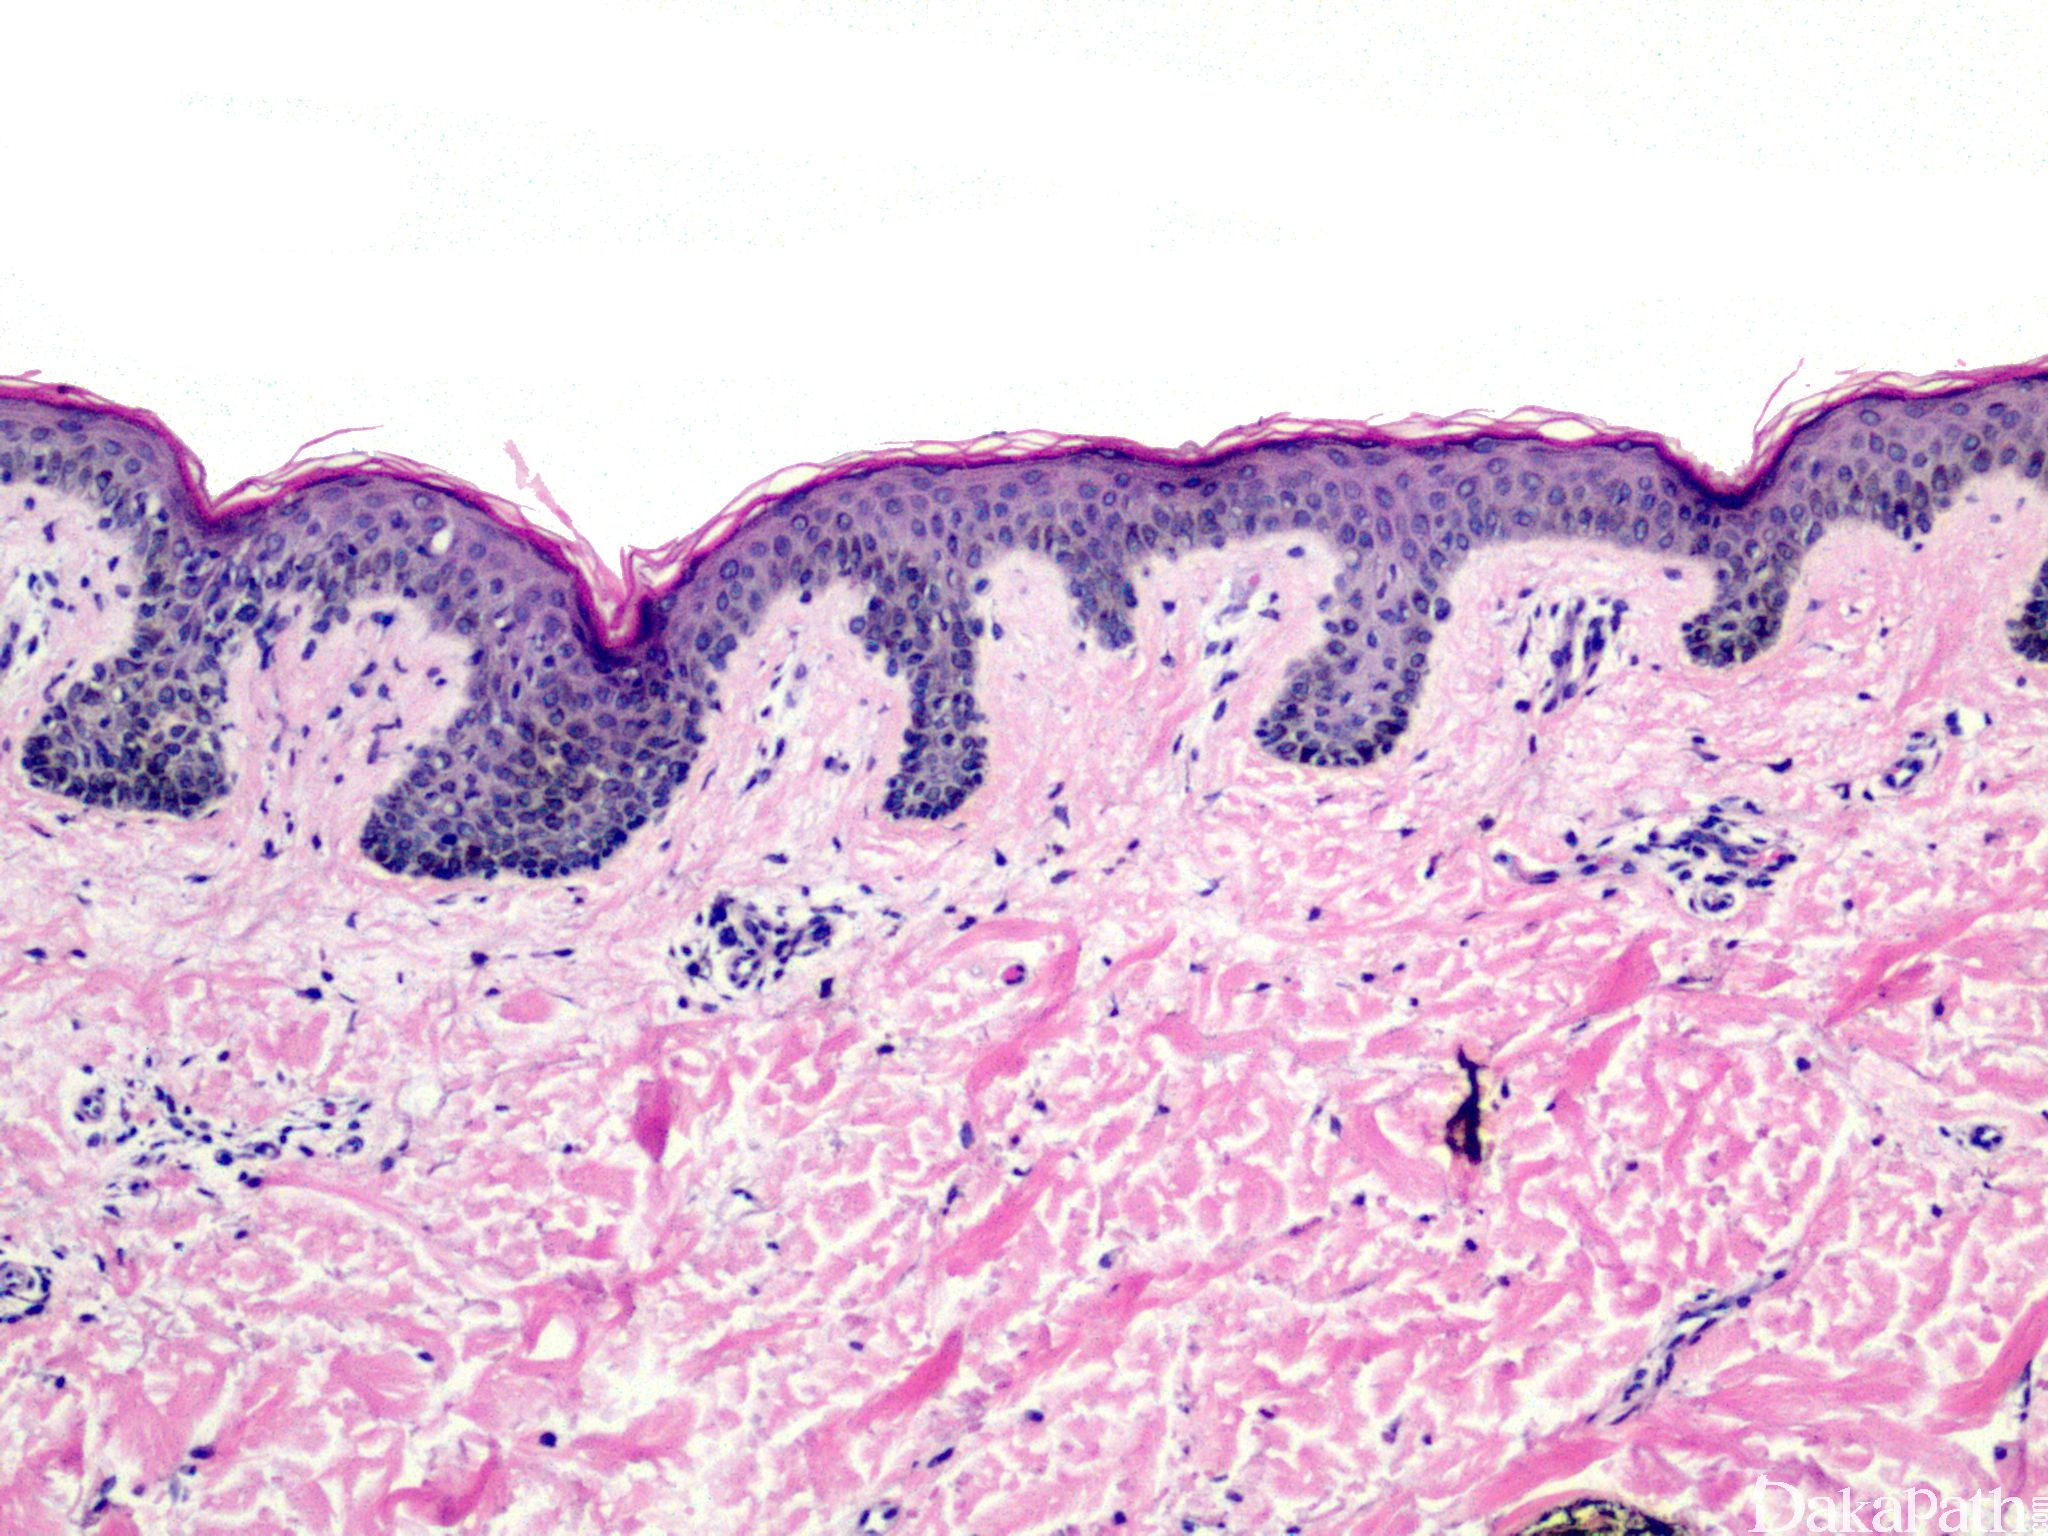

复合痣在表皮-真皮交界处雀斑样增生,细胞巢可融合或在上皮脚间架桥;

痣细胞巢大小和位置各异,边缘不规则,复合痣的交界处黑色素细胞增生,并延伸到真皮内痣细胞成分的边缘之外;

轻-中度细胞异型性,细胞核增大、深染、核仁明显;

间质淋巴细胞浸润、血管增生及真皮浅层板层状纤维增生。